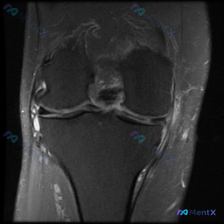

这是一张膝关节冠状位T2加权MRI图像,我们按结构逐一读片:

- 骨骼关节:股骨远端、胫骨近端骨髓无异常高信号,关节面平整,无明显骨赘增生或软骨下骨缺损

- 半月板:外侧半月板形态完整,无异常高信号;内侧半月板体部可见一条明显横行高信号影,贯穿半月板且到达关节囊边缘

- 韧带:内侧副韧带连续性完整,无异常肿胀高信号

- 软组织与积液:外侧胫骨平台外侧缘可见局部高信号,关节腔内可见少量液体信号,符合关节积液/软组织水肿表现